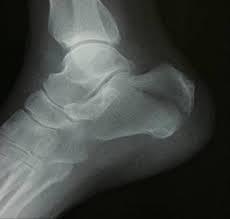

脱臼

脱臼の方のレントゲンです。

指の関節が外れているのが、確認できると思います。

提携医療機関より、レントゲンを見せて頂きました。

今後、医師の同意があり次第、リハビリになります。